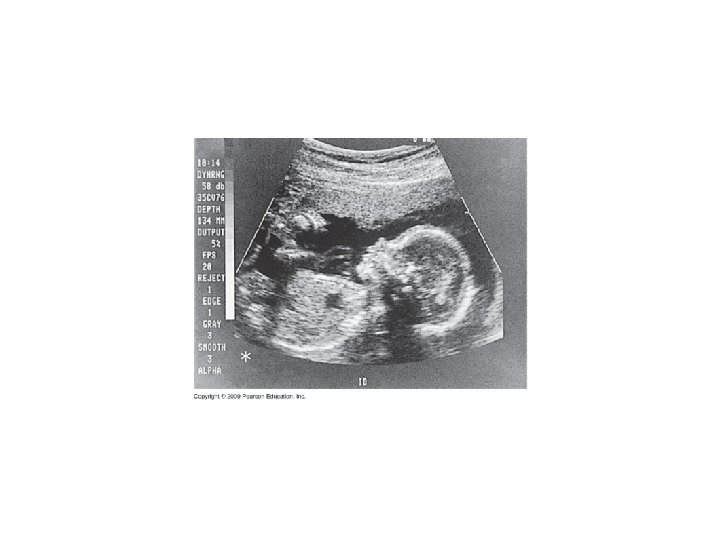

9. 10 CONNECTION: New technologies can provide insight into one’s genetic legacy Genetic testing of parents Fetal testing: biochemical and karyotype analyses – Amniocentesis – Chorionic villus sampling Maternal blood test Fetal imaging – Ultrasound – Fetoscopy Newborn screening Copyright © 2009 Pearson Education, Inc. Video: Ultrasound of Human Fetus

Chorionic villus sampling (CVS) Amniocentesis Needle inserted Ultrasound through abdomen to monitor extract amniotic fluid Ultrasound monitor Fetus Placenta Uterus Chorionic villi Cervix Suction tube inserted through cervix to extract tissue from chorionic villi Cervix Uterus Amniotic fluid Fetal cells Centrifugation Fetal cells Several weeks Biochemical tests Karyotyping Several hours